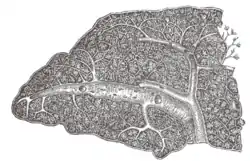

Transverse section of the human spleen, showing the distribution of the splenic artery and its branches. Section of the spleen, showing the termination of the small bloodvessels.

Section of the spleen, showing the termination of the small bloodvessels. Posterior abdominal wall, after removal of the peritoneum, showing kidneys, suprarenal capsules, and great vessels.